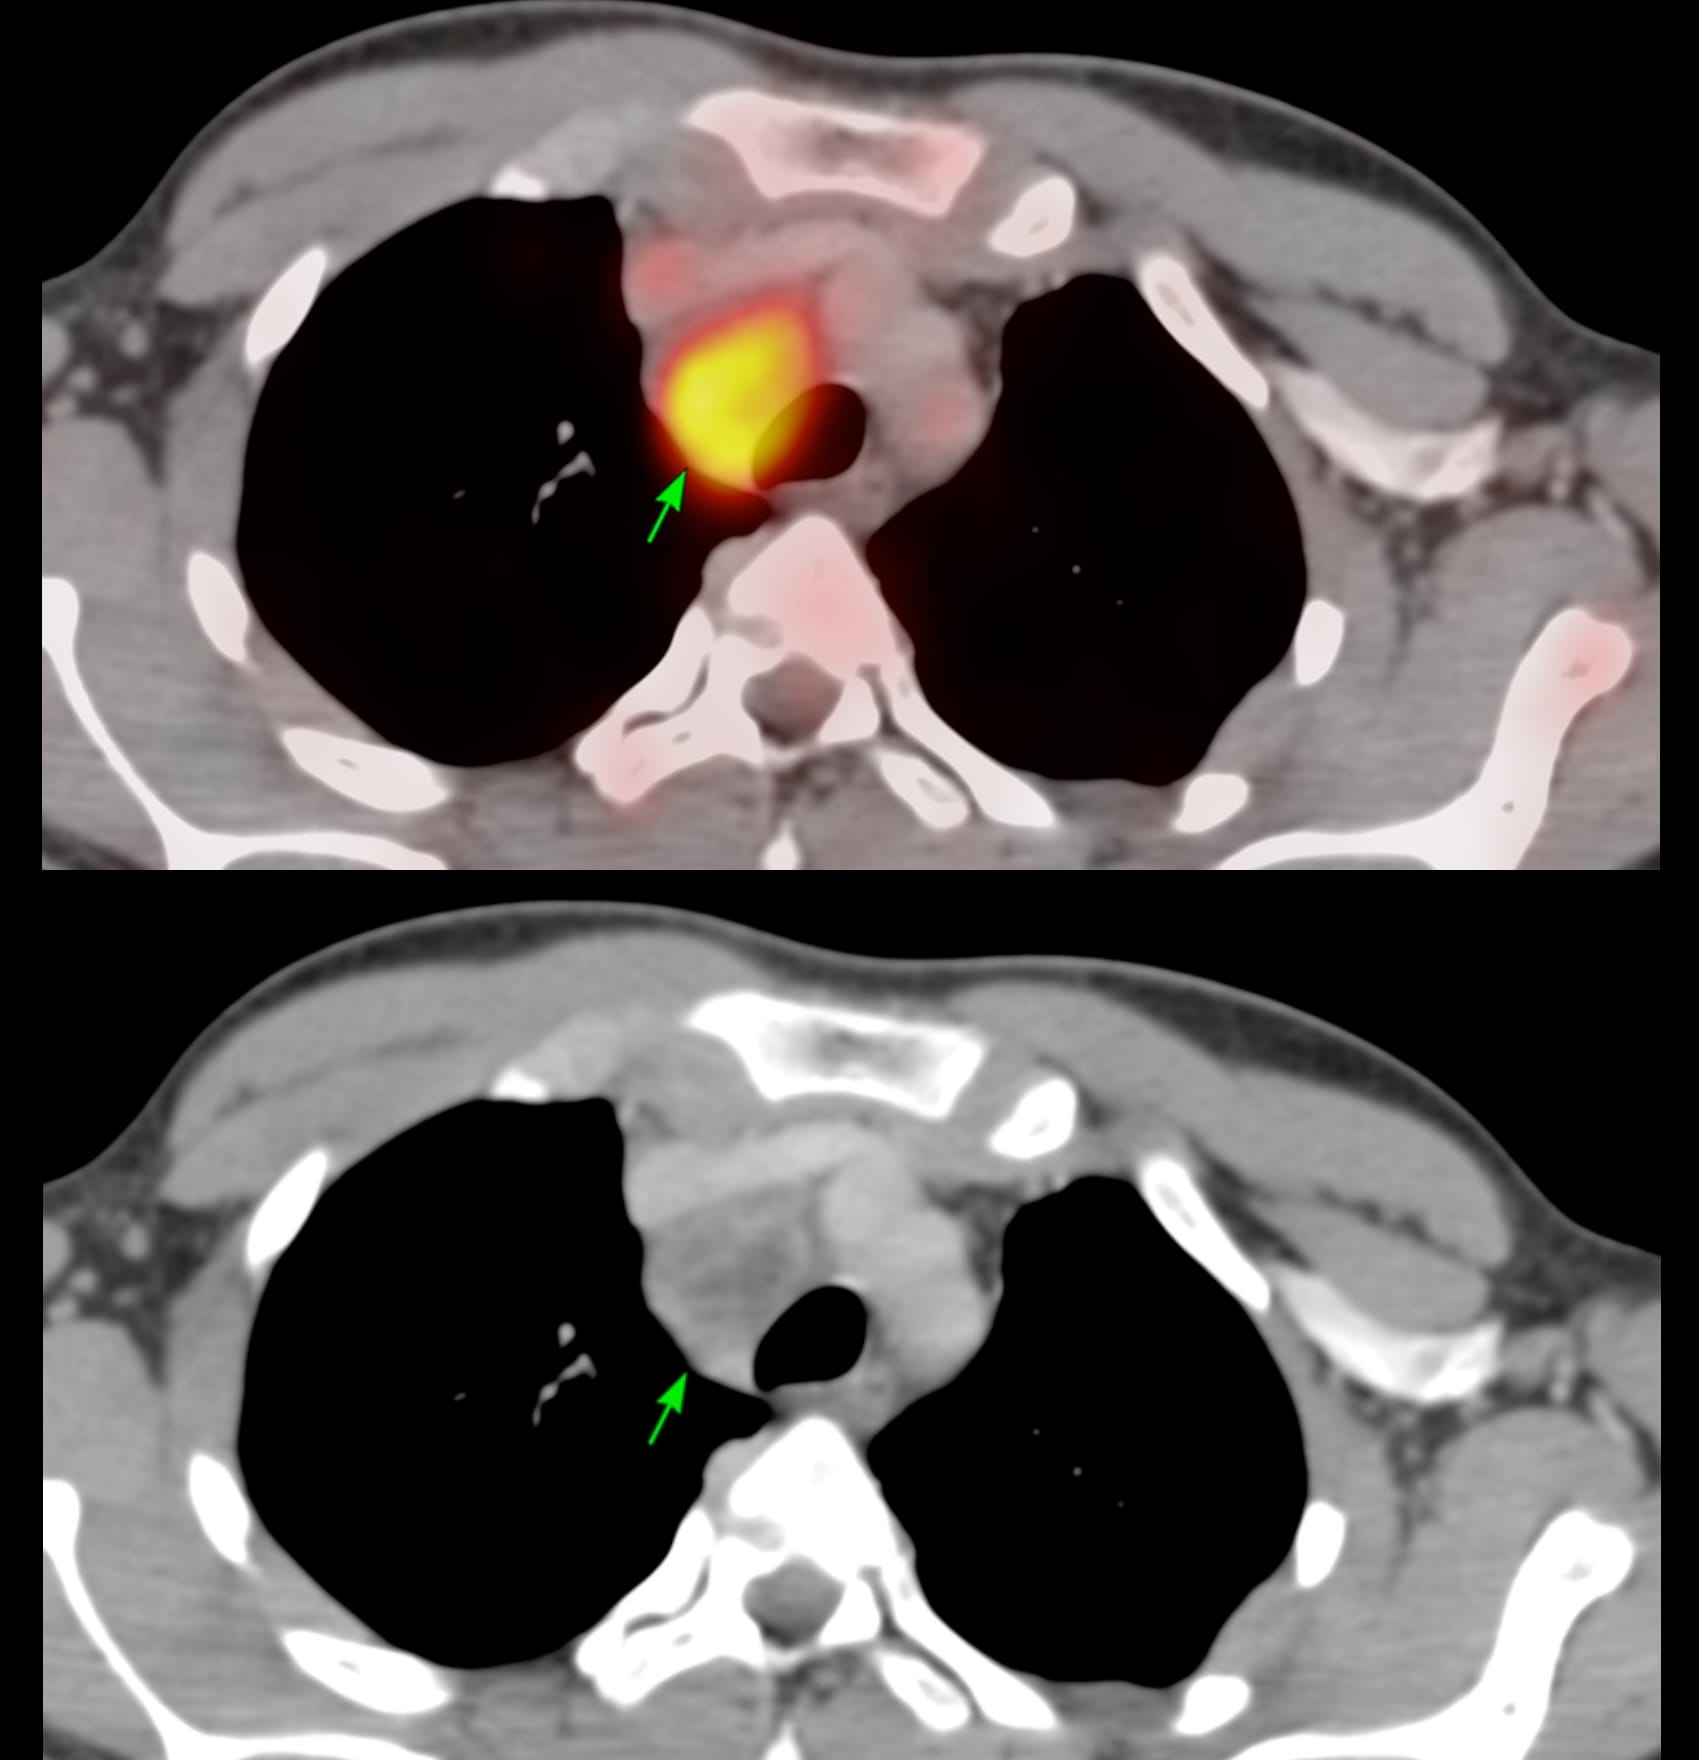

17-years old with fever had a PET/CT that showed a necrotic right paratracheal node - 4R - and was referred for a CT guided biopsy.

Arterial and venous phase studies in the prone position just prior to the biopsy showed the necrotic node well.